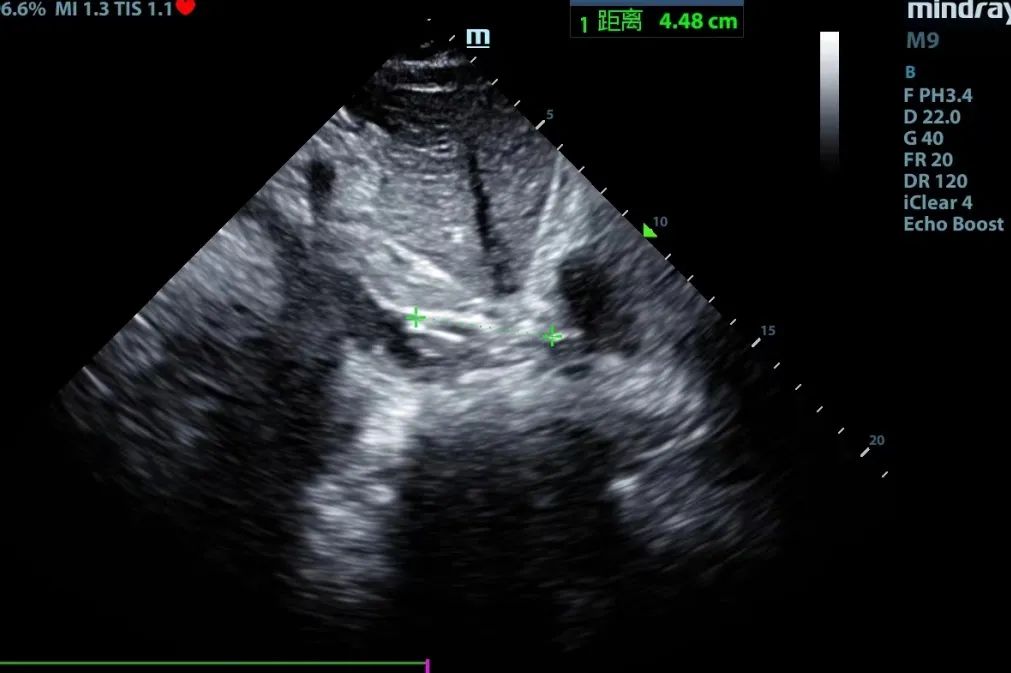

超声引导下,完成双腔颈静脉插管Crescent的置管和定位

张东山教授介绍:单管、双腔颈内插管较传统的双部位、单管插管技术难度更高;双腔插管需经颈内静脉、上腔静脉进入右心房后,再入下腔静脉,导管的三个开口需要分别位于上腔静脉、右心房、下腔静脉,且灌注口角度需要朝向三尖瓣,该要求对置管的深度及角度提出了极高要求,需要在超声引导下精准定位置管。但其优势也很明显: